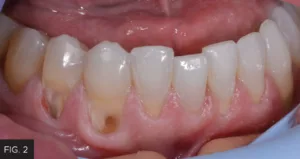

Initially, the decay was removed up to the free gingival margin. (FIG. 2) The retraction cord would not have retracted the tissue enough to complete the caries removal, so the laser procedure was utilized. The patient had already been anesthetized; however, additional anesthetic was placed in the buccal area adjacent to the prepared teeth. Prior to initiating laser treatment, a flexible periodontal probe (Hu-Friedy) was inserted into the periodontal pocket to determine where the level of the bone was positioned in order to prevent impingement of the biological width. The biologic width was determined to be approximately 2-3 mm, indicating adequate gingival tissue for a soft tissue laser procedure. In preparation for the procedure, the patient and all staff present had laser eye protection placed and a disposable, pre-bent tip was inserted into the Bluewave handpiece.